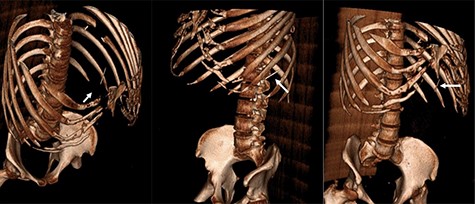

Two-mm axial sections from a CT scan demonstrating the linear hyperdensity traversing the spleen across multiple cross sections. (a) Section number 65 (b) section number 67 (c) section number 69 (d) section number 71 (e) section number 73 (f) section number 75.